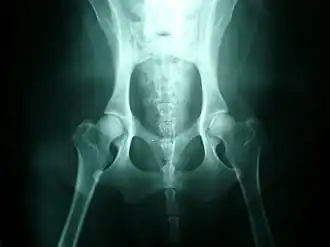

Fokmaatregelen

In een poging deze erfelijke ziekte weg te selecteren, worden röntgenfoto's gemaakt van de heupgewrichten van fokdieren voor die als fokdier ingeschreven worden in een stamboek. Een onderzoek op heupdysplasie is in het algemeen mogelijk op een leeftijd van 1 jaar.